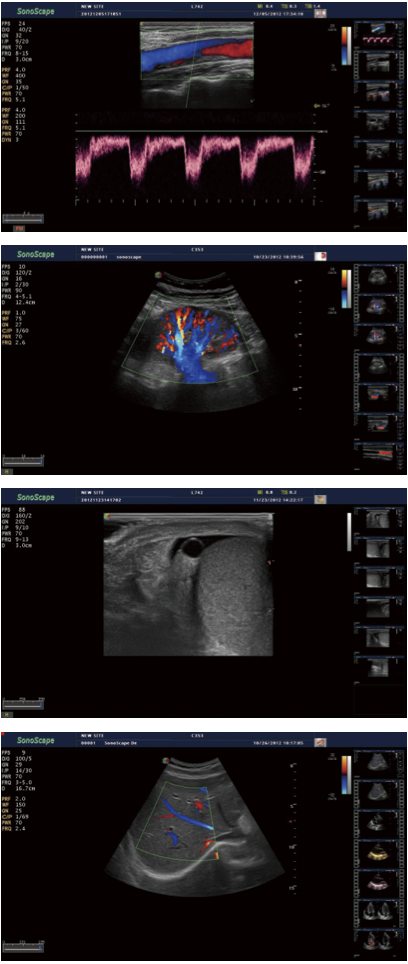

S40 es un sistema bastante completo de imágenes diseñado para satisfacer las necesidades más exigentes de hoy en día , desde abdominal profunda , vasculares superficiales para piezas pequeñas. Las configuraciones con tecnologías líderes tales como transductores de alta densidad y ancho de banda de planchar, así como las tecnologías innovadoras de imagen permiten S40 para mantener una excepcional calidad de imagen , tanto en campo cercano y lejano , lo que mejora la resolución y la penetración de una mayor confianza en el diagnóstico . Mejoras de flujo de trabajo , como la M- tuning una optimización automática de claves, seetings trabajo totalmente personalizado , teclas de función de un solo botón , dar una mayor coherencia del examen y solución eficiente para la ecografía .

La elastografía

SonoScape dota S40 con el nuevo método para apoyar el médico en la evaluación de la elasticidad del tejido . Las diferencias en la respuesta de los tejidos son detectados y visualizados en tiempo real por los algoritmos de elastografía a través de diferentes representaciones gráficas , que pueden ser particularmente útiles en el análisis de las estructuras de mama , tiroides y del aparato locomotor.

Pulso Inversion Harmonic Imaging

Gracias al impulso de inversión de imagen armónica y el gran ancho de banda de los transductores SonoScapes , las señales armónicas están completamente conservados sin degradación de la información acústica , que hace que sea posible para S40 a imagen detalles de alto nivel y mejorar la resolución de contraste mediante la reducción de ruido y el desorden en la visualización de las lesiones sutiles , piezas pequeñas , vascular y así sucesivamente .

Imaging Compuesto Espacial utiliza varias líneas de visión para la resolución de contraste óptimo , reducción de manchas y la detección de fronteras, con el que S40 es ideal para la imagen superficial y abdominal con mayor claridad y una mejor continuidad de las estructuras .

imagen panorámica

La S40 ofrece imágenes panorámicas en tiempo real para los órganos voluminosos y masas para la facilidad de medición y eficiencia diagnóstica , generando rápidamente información exacta sobre la posición de las lesiones .